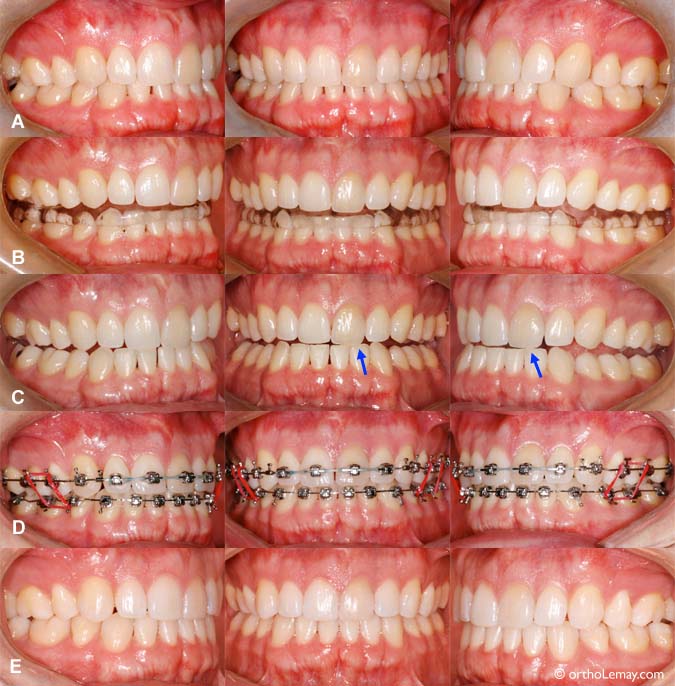

(A) Jeune homme de 28 ans se plaignant de maux de tête et de migraines. Il présente une occlusion relativement bonne mais les incisives supérieures et inférieures présentent un surplomb excessif (overbite), (B) Le port d’une plaque occlusale pendant plusieurs mois a permis de soulager les symptômes. (C) Après le port de la plaque, l’occlusion révèle une toute autre relation que l’occlusion initiale. Il n’y a qu’un seul contact entre les dents antérieures (flèche) et pas de contacts postérieurs. Pendant la fonction, le patient doit donc forcer pour que les dents postérieures entrent en contact, ce qui pouvait contribuer à l’apparition de symptômes articulaires ou autres. (D) La phase orthodontique corrective permit d’optimiser la position des dents tout en gardant la position de mâchoire confortable qui fut obtenue par le port de la plaque occlusale. (E) Occlusion finale; le surplomb vertical est diminué et l’inclinaison des dents antérieures a été modifié.